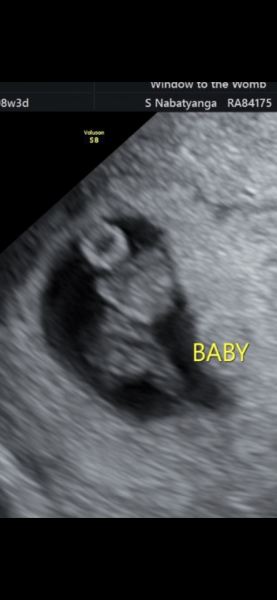

hol92 · 17/02/2024 15:12

Measuring a few days behind what I thought but all good otherwise :) why can't we have a scan every week and for free haha

Due September 2024 - Part 4! 🤰🏻💙🩷